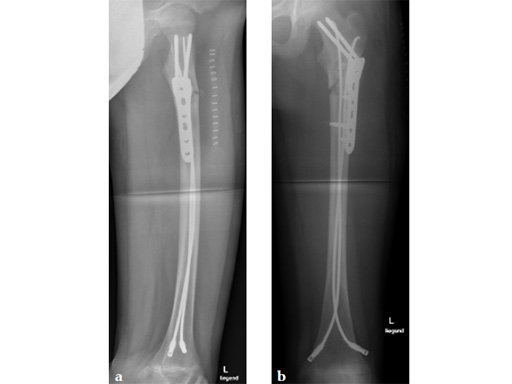

Case 1: LCP PHP 130. A 15-year-old boy sustained a refracture of a pathological fracture of the subtrochanteric region following a severe trauma, previously fixed with ESIN , diagnosis: juvenile bone cyst.

Case provided by Theddy Slongo, Bern, Switzerland